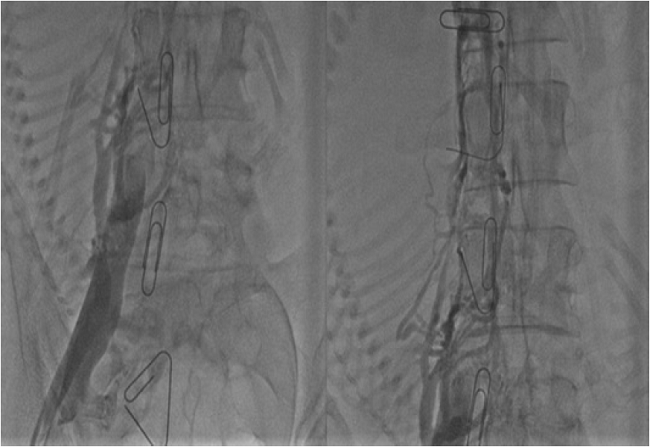

Por alta sospecha clínica de TVP se realizó ecografía doppler de miembros inferiores que reportó TVP activa de unión safeno-femoral y femoral común izquierda, por lo cual se inició heparina de bajo peso molecular (HBPM) a dosis de 1 mg/kg cada 12 h. Posteriormente, la paciente presentó regularización de actividad uterina; ante el riesgo de sangrado masivo por la anticoagulación y la posibilidad de TEP masivo por descompresión uterina, se consideró colocación de filtro de vena cava temporal, sin embargo, durante el procedimiento se evidenció que la trombosis se extendía hasta la vena cava inferior (figura 1), contraindicándose su implantación.

Durante el procedimiento no fue suspendida la heparina de bajo peso molecular. A las 30 h de la trombolisis presentó sangrado vaginal y frecuencia cardiaca de 91 lpm, tensión arterial de 80/40 mm/ hg, frecuencia respiratoria de 22 rpm y saturación de oxígeno del 92 %. Se diagnosticó choque hipovolémico por hematoma disecante del canal vaginal; se decidió interconsulta con el servicio de hematología, quienes ordenaron realizar transfusión de 2 unidades de glóbulos rojos por caída de hemoglobina mayor a 2 g, reanimación con líquidos cristaloides, empaquetamiento vaginal y colocación de balón de Backri. A las doce horas posteriores, por orden del servicio de hematología, se decide iniciar manejo con enoxaparina a 1 mg/kg cada 12 h, sin nuevos episodios de sangrado. Se eligió la heparina de bajo peso molecular debido a que la incidencia de eventos tromboembólicos venosos recurrentes es menor en personas tratadas con enoxaparina que con heparina no fraccionada. Se llevó a flebografía para definir posibilidad de trombectomía, que se encontró contraindicada por trombos en todo el eje iliaco izquierdo con drenaje por circulación colateral (figura 2), por lo cual se decidió continuar con anticoagulación.